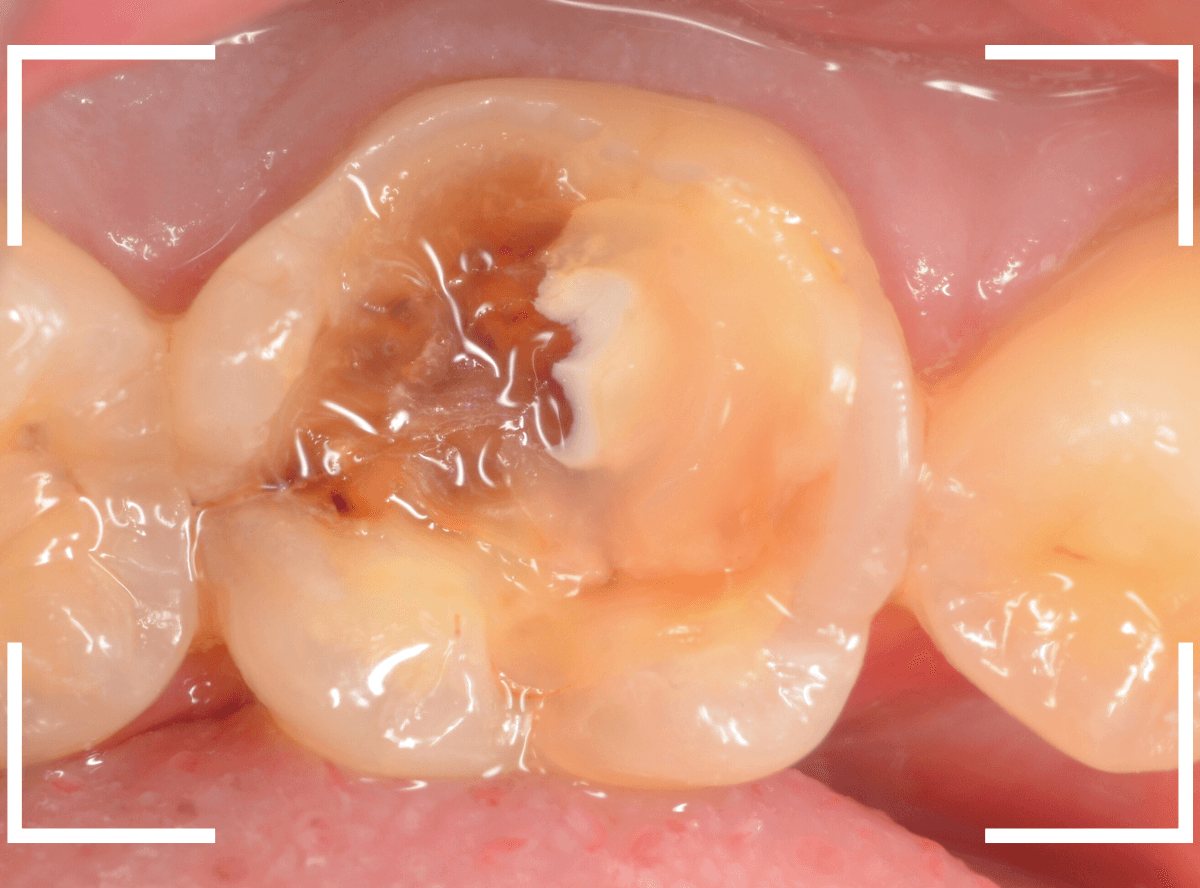

Case.18 虫歯なのは間違いないが、境界がはっきりしない

「つめものが外れて、噛むと痛い」という訴えで来院された患者さんさんです。

一見で、表面が虫歯になっているのと、レジンが劣化しているのがわかります。

レントゲン写真で確認します。

〇部が当該の歯です。

症状もあるので、虫歯が深そうですが、全体がもやっとして、どこからどこまで虫歯なのかはっきりわかりません。

まれに、こんな時もあります。

レジンを外し、虫歯の処置を進めます。

慎重に虫歯を除去し、一安心か、という寸前で(〇部、小さく出血しているところ)露髄してきました。

神経を除去しないとダメかもしれません。。。

神経を保護するお薬をつめて、経過観察します。

痛みが出ませんように。。。